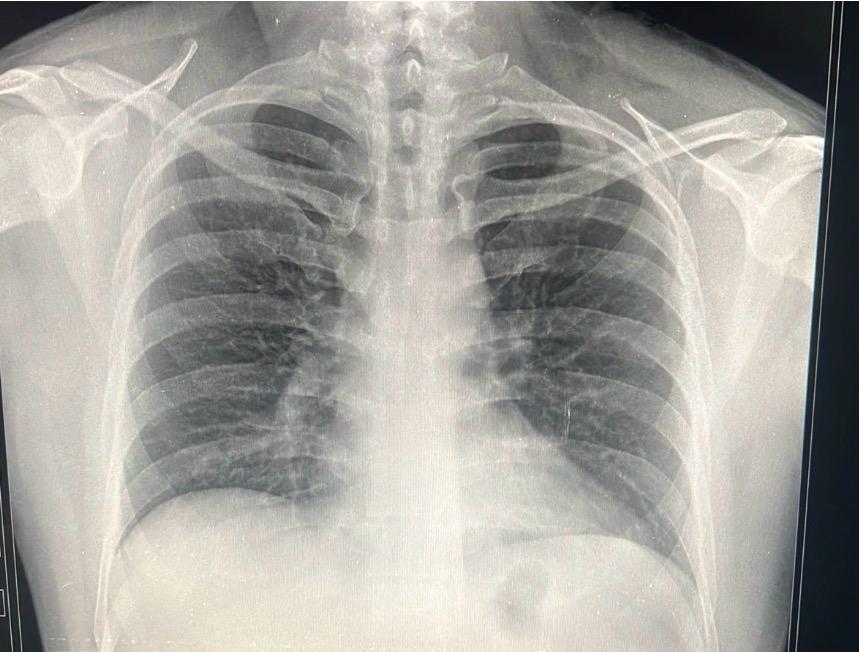

Radiografía Tórax

Estudios especializados para revisar el funcionamiento de los pulmones.